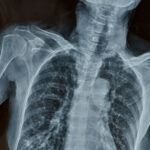

The patient presented to hospital with sudden onset of right-sided weakness, slurred speech and facial droop — classic symptoms of acute ischaemic stroke. Despite these red-flag signs of stroke, medical negligence occurred when the emergency department failed to recognise the condition and initiate the correct urgent pathway.

The patient was assessed but not treated as a time-critical stroke case. No immediate CT head scan was performed within the required timeframe, and thrombolysis or thrombectomy was not considered. Medical negligence in failing to follow the national stroke protocol allowed the clot to remain untreated, leading to progression of the infarct and significantly worse brain damage than would have occurred with prompt intervention.

The patient was eventually admitted to a ward but without the benefit of hyperacute stroke therapies. By the time the diagnosis was confirmed the window for clot-busting treatment and clot retrieval had closed. Medical negligence in the initial emergency assessment directly contributed to the extent of the brain injury sustained.